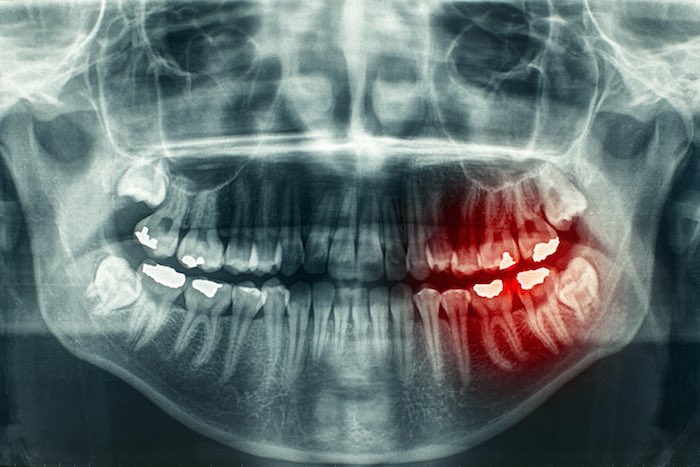

MUELAS DEL JUICIO

Hace mil 500 años las personas necesitaban de estas muelas ubicadas en la parte posterior de la boca para masticar alimentos más duros. Sin embargo, la dieta del hombre cambió y estas siguen saliendo entre las edades de 18 a 26 años.

“Ahorita no tenemos el espacio para que quepan las muelas del juicio, entonces, se recomienda quitarlas. Sin embargo, hay veces que salen derechitas y las personas tienen el espacio para que salgan, entonces no hay problema”, explica Sánchez.

No tratar una muela del juicio que sale en dirección equivocada puede recorrer el resto de dientes, lo que también genera otras complicaciones como gingivitis, por lo que acuden con un especialista maxilofacial para su extracción.

“Pueden costar alrededor de 2 mil pesos la cirugía de cada una y son cuatro”, dice la dentista.